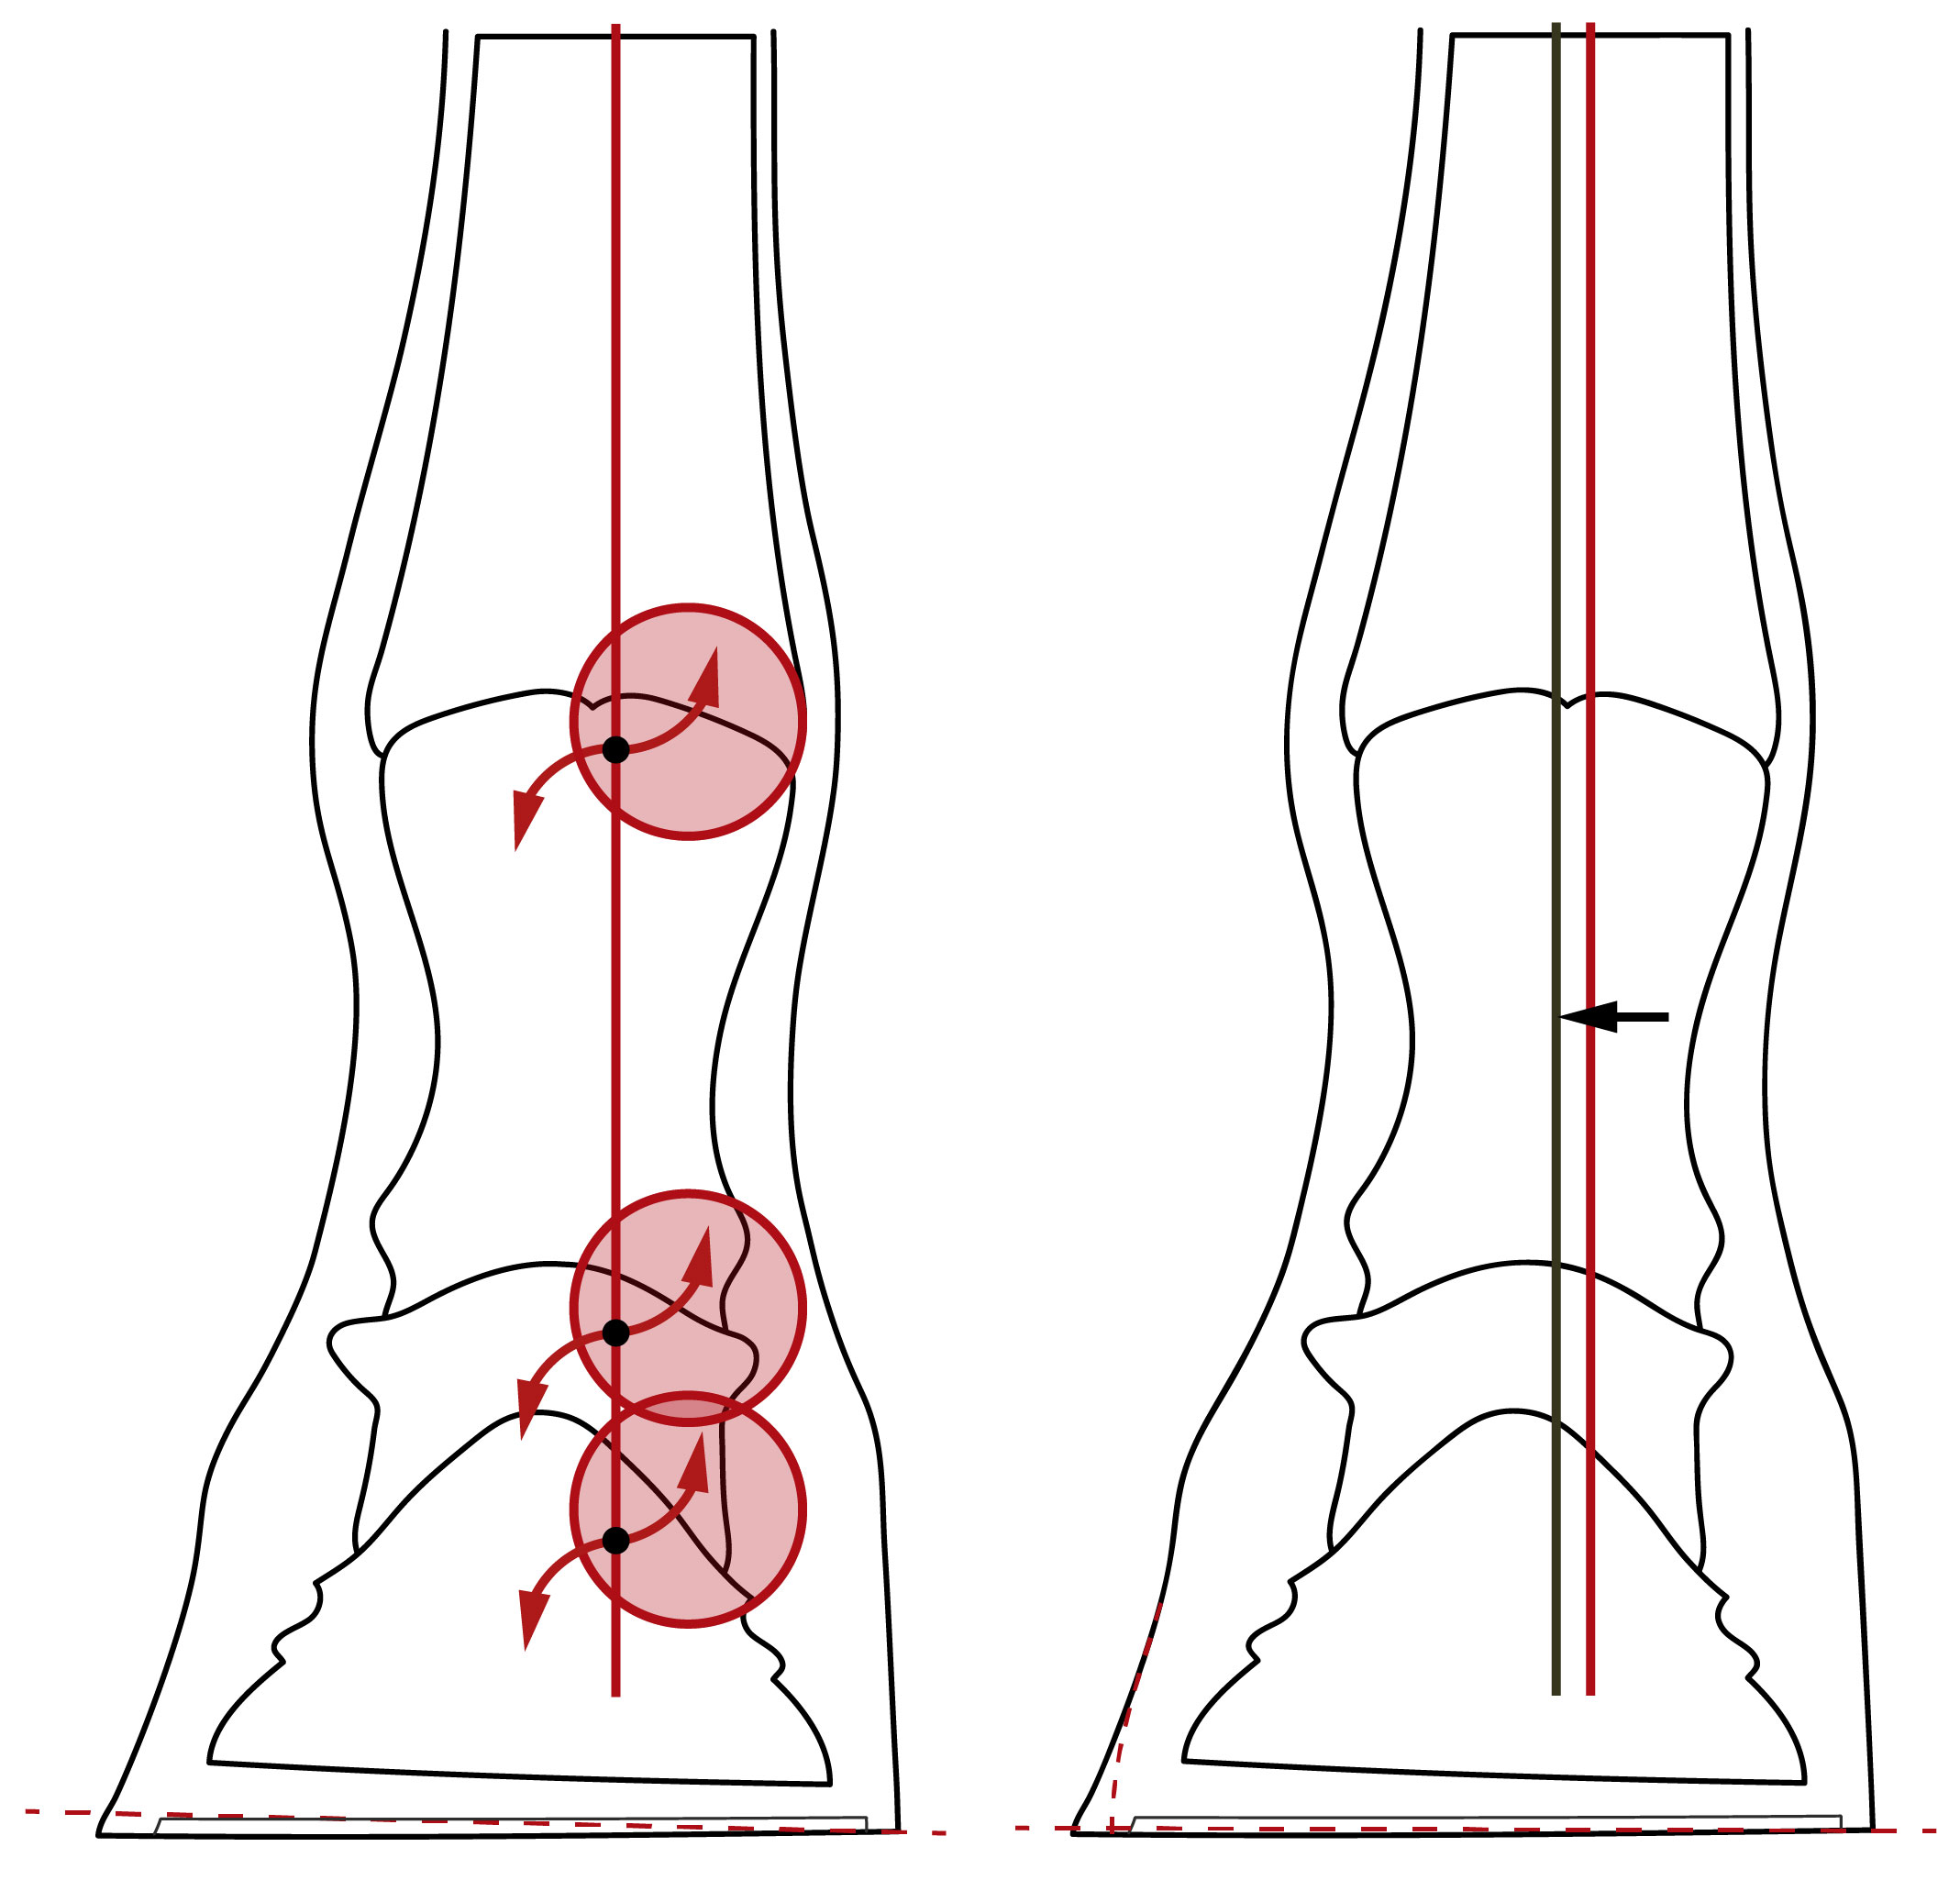

Weil die einwirkenden Kräfte nun nicht mehr mittig, sondern zur Seite versetzt in den Huf eingeleitet werden (siehe rote Linie der folgenden Illustration rechts), verändern sich mit der Zeit sogar die Knochen der Knochensäule. Die verschobene Belastung führt zwangsläufig zu einer ungleichmäßigen Belastung der Gelenke, die von den Knorpeln der Scharniergelenke und des Sattelgelenks zwischen Huf- und Kronbein kompensiert werden muss (rote Kreise).

Illustration einer gleichmäßigen und einer ungleichmäßigen Lastverteilung

Links: Gleichmäßige mediolaterale Belastung mit einer mittigen Einleitung der Kräfte und einer gleichmäßigen Belastung der Gelenke.

Rechts: Einseitige Mehrbelastung mit einer zur Seite verschobenen Einleitung der Kräfte und einer ungleichmäßigen Belastung der Gelenke.

Versucht man die zur Seite verschobene mediolaterale Lastverteilung durch ein erhebliches Kürzen der weniger belasteten Hufhälfte wieder auszugleichen, gelingt das zwar äußerlich, doch die inneren Strukturen werden durch diese abrupte Umstellung erheblich überlastet. Da sich die inneren Strukturen auf die verschobene Einleitung der Kräfte (rote Linie in der folgenden Abbildung links) vor dem einseitigen Kürzen eingestellt haben, müssen die Elastizität des Hufes und die Gelenkknorpel den abrupten Stellungswechsel umgehend ausgleichen.

Das führt dazu, dass sich die Belastung der Gelenke um den seitlichen Drehpunkt des jeweiligen Gelenks herum (schwarze Punkte) noch weiter auf die sowieso schon mehr belastete Seite verschiebt (rote Kreise). Die Elastizität des Hufes und die Gelenkknorpel werden durch die abrupte Umstellung überfordert.

Im schlimmsten Fall wird die mehr belastete Seite durch das einseitige Kürzen sogar noch mehr belastet, da die gekürzte Hufhälfte möglicherweise noch weniger Last aufnehmen kann als zuvor. Ob das tatsächlich so ist, hängt davon ab, wie sehr sich die inneren Strukturen bereits der Belastungssituation angepasst haben und wie viel die Elastizität des Hufes und die Gelenkknorpel ausgleichen können. Die Gefahr einer Verschlechterung der Belastungssituation ist groß. Deshalb sollte ein Huf nicht einseitig gekürzt werden, zumindest nicht erheblich.

Die huforthopädische Lösung

Die korrekte Lösung einer seitlichen Überlastung liegt deshalb nicht im abrupten Stellungswechseln, sondern primär in einer schonenden Umstellung durch eine sinnvolle Abriebsteuerung, wie die folgende Illustration rechts andeutet (gestrichelte Linie an der Hufwand). Wird der Abrieb der weniger belasteten Hufhälfte gefördert, kann sich der Huf Schritt für Schritt über mehrere Bearbeitungszyklen hinweg selbst ausbalancieren. Weder die Elastizität des Hufes noch die Gelenkknorpel werden dadurch überfordert. Wird die Hufwand der weniger belasteten Seite darüber hinaus elliptisch geformt, kann sie wieder mehr Last tragen und dadurch die mehr belastete Seite entlasten. Die inneren Strukturen können sich langsam an die gleichmäßigere Lastverteilung gewöhnen. Die Einleitung der Kräfte verschiebt sich langsam wieder in Richtung Mitte (von der roten zur grünen Linie).

Illustration zum Vergleich des üblichen Bearbeitungsansatzes eines einseitigen Hufes mit dem huforthopädischen Ansatz

Links: Das erhebliche einseitige Kürzen führt zu einem abrupten Stellungswechsel, überfordert die Elastizität des Hufes und verstärkt die ungleichmäßige Belastung der Gelenke.

Rechts: Das Fördern des Abriebs, das elliptische Formen der Hufwand und das minimale Kürzen im Rahmen der Elastizität des Hufes führt zu einem schonenden Ausbalancieren des Hufes.